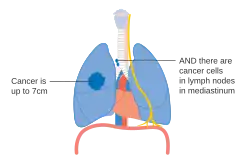

Stage IIB lung cancer

Stage IIB lung cancer -

One option for stage IIB lung cancer, with T2b; but if tumor is within 2 cm of the carina, this is stage 3

One option for stage IIB lung cancer, with T2b; but if tumor is within 2 cm of the carina, this is stage 3 -